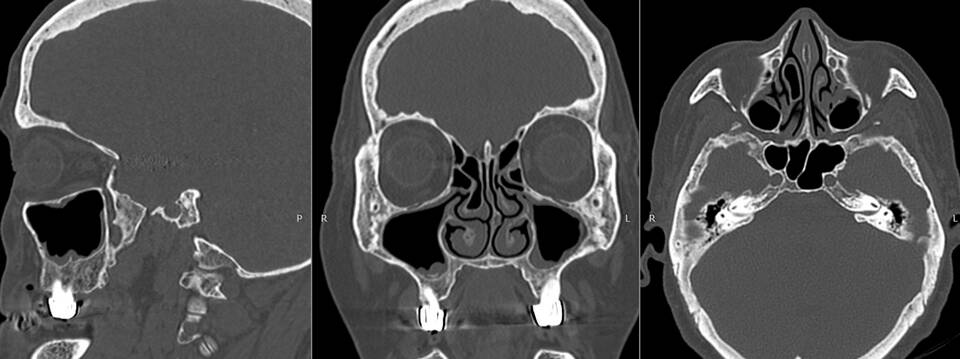

- Точная визуализация костных структур